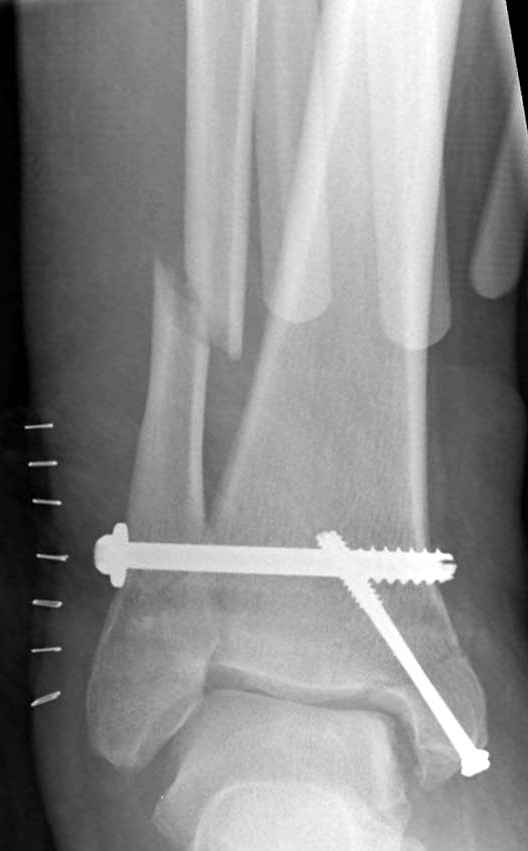

Ниже рентгенограммы

До операции 28 июля

Операция 29 июля

Риторический вопрос - в каком руководстве рекомендован такой способ остеосинтеза наружной лодыжки?

Очевидно, такой результат операции был запрограммирован. При невосстановленной длине и практически нефиксированной малоберцовой кости (этот кортикальный винт - как карандаш в стакане), при неустраненном подвывихе, невправленной и тоже нефиксированной внутренней лодыжке нет стабильной вилки сустава. Если такую операцию сделать даже сразу, а не через 4 месяца, то результат ожидаем

тот же.

Вообще говоря, такое повреждение вполне успешно можно лечить без операции - если 6 недель подержать в гипсовом "сапожке" с хорошо устраненным подвывихом. Вероятное несращение внутренней лодыжки не обязательно компрометирует результат.

Ну а уж если выбран остеосинтез - нначать надо было с репозиции малоберцовой кости с точным восстановлением длины, с фиксацией треть-трубчатой пластиной по задней поверхности. Позиционный винт

избыточен - повреждение практически подсиндесмозное. А если бы

действительно было повреждение синдесмоза - в 4 месяца позиционный винт - не решение. Внутренню лодыжку такую - надо было бы спицами и проволочной петлей. Извините за эти банальности.